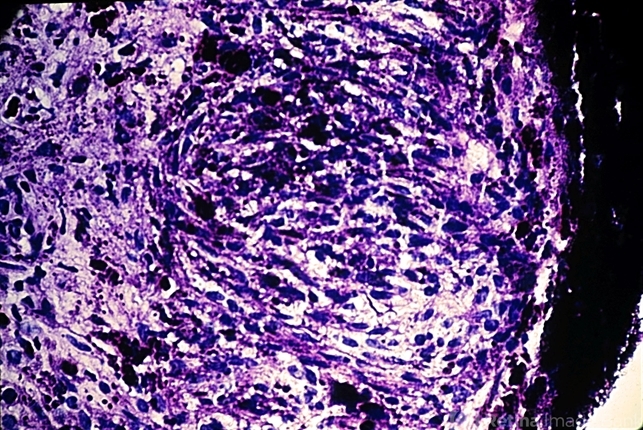

- melanoma, iris melanoma, spindle cells

- The vast majority of iris melanomas are composed of spindle A and/or spindle B cells and are relatively benign.